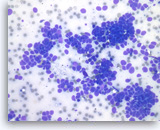

Plasma cell neoplasm,

Pancreas FNA, Direct Smear.

The aspirates show dispersed single cells with a prominent plasmacytoid appearance. The tumor cells vary slightly in size. Rare mitoses are seen.

20X

Plasma cell neoplasm,

Pancreas FNA, Direct Smear.

The aspirates show dispersed single cells with a prominent plasmacytoid appearance. The tumor cells vary slightly in size. Rare mitoses are seen.

20X

Plasma cell neoplasm,

Pancreas FNA, Direct Smear.

The tumor cells show perinuclear hof (clearing). Binucleated tumor cells are occasionally seen. Scattered lymphoglandular bodies are seen in the background.

40X

Plasma cell neoplasm,

Pancreas FNA, Direct Smear.

The tumor cells show perinuclear hof (clearing). Binucleated tumor cells are occasionally seen. Scattered lymphoglandular bodies are seen in the background.

40X

Plasma cell neoplasm,

Pancreas FNA, Direct Smear.

The tumor cells have eccentrically located round nuclei with clumped chromatin and small nucleoli.

40X

Plasma cell neoplasm,

Pancreas FNA, Direct Smear.

The tumor cells have eccentrically located round nuclei with clumped chromatin and small nucleoli.

40X

Plasma cell neoplasm,

Pancreas FNA, Cell Block.

Single tumor cells show eccentric nuclei and occasional binucleation. Flow cytometry demonstrate CD38 positive B-cells without surface immunoglobulin expression. The cytomorphologic features along with flow cytometry results are consistent with plasma cell neoplasm. CD138 immunostain can be performed on the cell block section to support the diagnosis if needed.

40X

Plasma cell neoplasm,

Pancreas FNA, Cell Block.

Single tumor cells show eccentric nuclei and occasional binucleation. Flow cytometry demonstrate CD38 positive B-cells without surface immunoglobulin expression. The cytomorphologic features along with flow cytometry results are consistent with plasma cell neoplasm. CD138 immunostain can be performed on the cell block section to support the diagnosis if needed.

40X